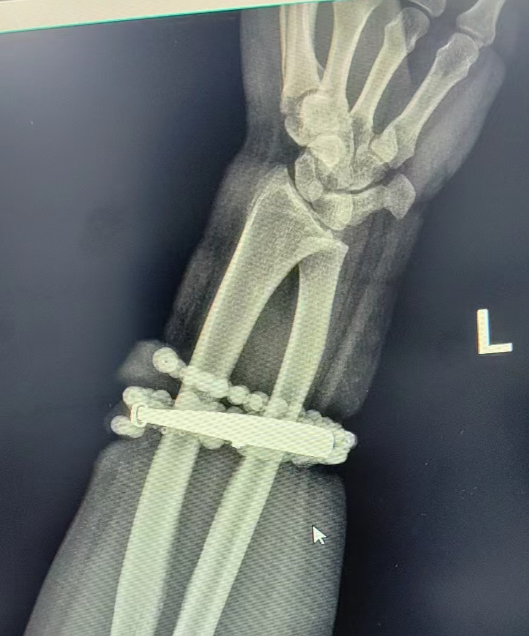

戴了十年没摘的手镯、串珠竟长进了肉里,还发炎了!近日,福建省宁德市闽东医院创伤骨科、手显微外科就接诊了这样一位患者。

然而,就在两周前,龚女士的情况急转直下:手腕不仅疼痛加剧,还出现了明显的红肿,甚至有脓液渗出。她这才惊觉——手镯和串珠,已经有一部分“长”进了肉里,根本取不下来了!

“这是典型的首饰长期压迫、摩擦,加上细菌感染,引发的慢性炎症和肉芽组织增生。”医生介绍,此时,手镯和串珠已经成了一个不断刺激皮肤、污染伤口的“病灶”,如果不尽快手术取出,感染可能进一步扩散,甚至危及生命或影响手臂功能。

经过一个多小时的手术,医生们将手镯和串珠从厚厚的增生组织中完整剥离出来。目前,龚女士恢复良好,已顺利出院。